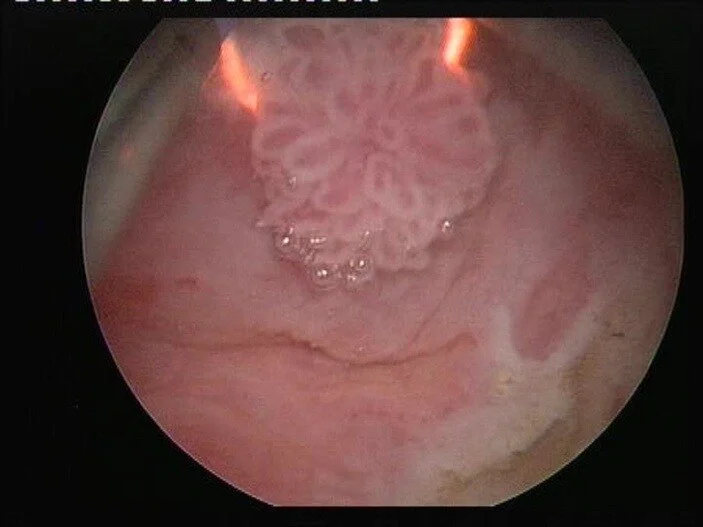

Cistoscopia

El estudio más importante. Introducimos una cámara ultrafina y flexible por la uretra para observar directamente todo el interior de la vejiga en tiempo real, sin dolor.

Resección Transuretral (RTU-V)

Es una cirugía endoscópica sin incisiones externas. A través de la uretra, utilizamos un asa eléctrica o láser para "raspar" y eliminar el tumor desde su base. El tejido se envía a patología.